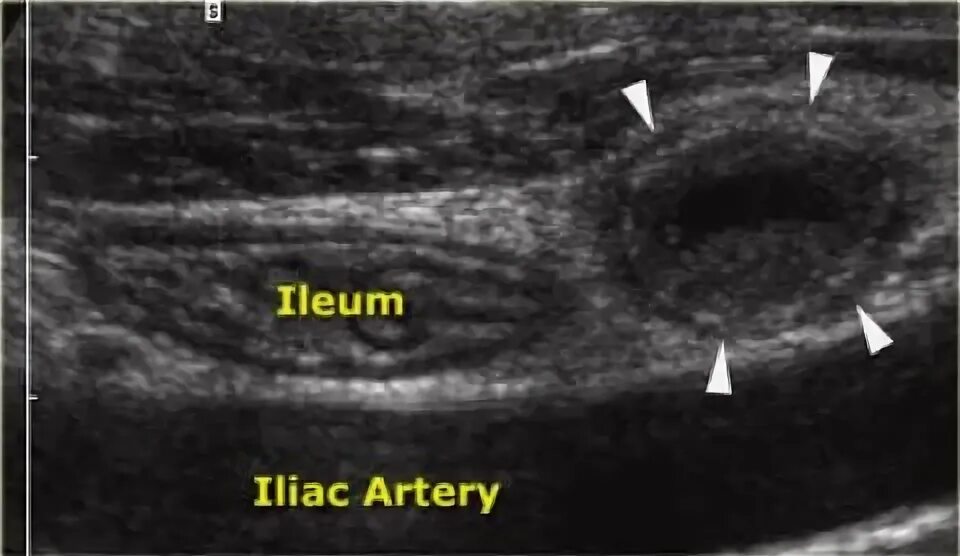

Какое узи при аппендиците